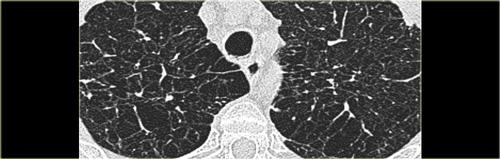

Dưới đây là hai ví dụ về viêm phổi quá mẫn bán cấp.

Có thể thấy các nốt trung tâm tiểu thùy bờ không rõ dạng kính mờ.

Đây là một trường hợp khác của viêm phổi quá mẫn bán cấp.

Có thể thấy hình mờ mờ nhạt ở trung tâm các tiểu thùy thứ cấp (mũi tên) với vùng dưới màng phổi được bảo tồn.